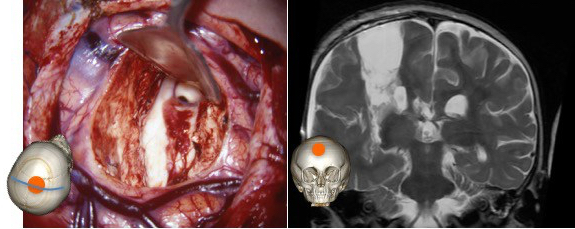

la chirurgie

le principe est de déconnecter toutes les voies de conduction de la substance blanche en laissant le thalamus seul en place.

il existe plusieurs techniques possibles ; nous utilisons la technique développée par O Delalande, avec :

- corticectomie en région centrale

- callosotomie vers l’avant jusqu’au bec du corps calleux (repère : l’artère communicante antérieure)

- callosotomie postérieure jusqu’au selenium (repère : la veine de Galien)

- section de la corona radiata en rejoignant la corne temporale et le corps du ventricule (repère antérieur : l’artère sylvienne)

- section du fornix et du gyrus rectus (repère : l’artère cérébrale antérieure)